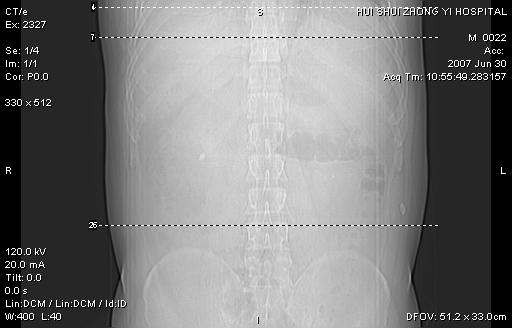

男,44岁,体检。

双肾结石

双侧肾盂、输尿管内结石,双侧肾脏轮廓呈波浪状,可能以前有过感染的

支持双肾结石

双肾结石.

双侧肾盂结石。